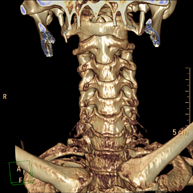

- Angio – TC Troncos Supraaórticos Prueba radiológica que consiste en obtener imágenes de las arterias carótidas del cuello de alta definición anatómica mediante el empleo de un equipo de TC (Tomografía Computarizada) y la inyección de contraste intravenoso. Posteriormente, las imágenes son reconstruidas en tres dimensiones (3D). Indicaciones: accidente vascular cerebral agudo, accidente vascular transitorio, soplo carotídeo. Prueba radiológica que consiste en obtener imágenes de las arterias carótidas del cuello de alta definición anatómica mediante el empleo de un equipo de TC (Tomografía Computarizada) y la inyección de contraste intravenoso. Posteriormente, las imágenes son reconstruidas en tres dimensiones (3D). Indicaciones: accidente vascular cerebral agudo, accidente vascular transitorio, soplo carotídeo.

- TC Columna cervical Prueba radiológica que consiste en obtener imágenes de las vertebras cervicales de alta definición anatómica mediante el empleo de un equipo de TC (Tomografía Computarizada). Indicaciones: cervicalgia sin/con irradiación a brazos, traumatismo. Prueba radiológica que consiste en obtener imágenes de las vertebras cervicales de alta definición anatómica mediante el empleo de un equipo de TC (Tomografía Computarizada). Indicaciones: cervicalgia sin/con irradiación a brazos, traumatismo.